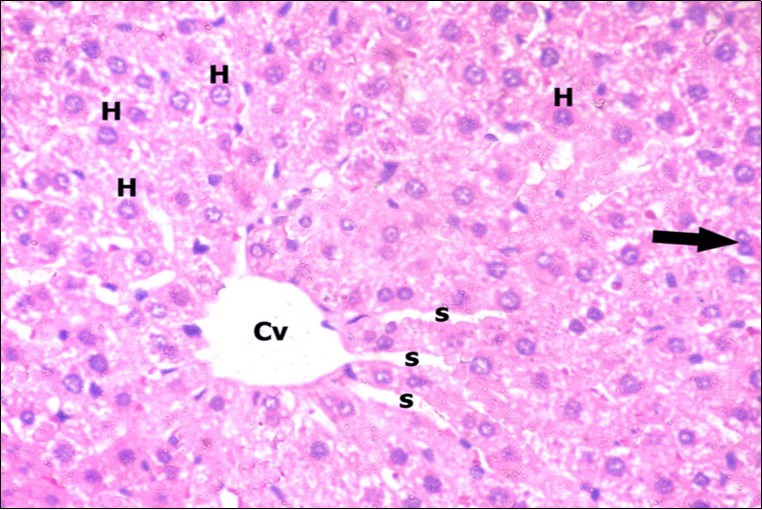

Examination of H&E stained sections of the 1st group (control group) revealed hepatic architecture of tightly packed cords of hepatocyte with vesicular nuclei and acidophilic cytoplasm radiating from the central vein (Figure 1). Portal area was composed of a portal vein, branch of hepatic artery and bile duct lined by single cuboidal cells with dark rounded nuclei. Blood sinusoids with their endothelial lining of Kuppfer cells were noticed in between hepatic cords (Figure 2). Examination of the liver sections of the 2nd group (vitamin E treated group) showed nearly the same histological features as the 1st group. The 3rd group (ZnONPs-treated group) showed a marked loss of the normal liver arrangement with dilated congested central veins and blood sinusoids. Most of hepatocytes had large cytoplasmic vacuoles and darkly stained nuclei other hepatocytes were ballooned (Figure 3). The portal area showed dilated congested portal vein with proliferation of bile duct, necrotic foci in between the hepatocytes with inflammatory cellular infiltration (Figure 4). The portal area showed also elongation of the endothelial lining of dilated congested portal vein and increasing amount of connective tissue fibers (Figure 5). There was congested hepatic artery with increasing thickness of its muscular layer (Figure 6). Bile duct showed proliferation with stratification of its epithelial lining (Figure 7).

Figure 1.A photomicrograph of a section in the liver of a control adult albino rat showing polygonal hepatocytes (H) radiating from central vein (Cv) with rounded vesicular nuclei and acidophilic cytoplasm. Narrow radiating blood sinusoids (s) in between liver cords and their lining endothelium are noticed. Binucleated cell is also seen (thick arrow). (H&E X400)